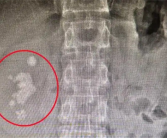

男子查出肾结石未重视拖成大麻烦:发展为铸型结石填满肾脏!

据媒体报道,长沙的向先生十多年前就查出右肾结石,时常感到腰部隐痛,但一直未作处理。直到近期腰部胀痛加剧,影响到日常工作,他才决定就医。没想到检查发现,结石已长成...